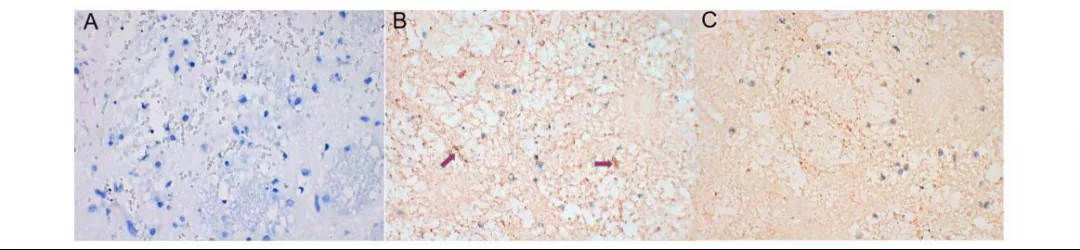

图片图6:在丁苯酞干预后AQP4较脑出血对照组降低(箭头指示的黄色染色部分是AQP4的所在位置,蓝色部分是细胞核)。A.假手术组;B.脑出血3天对照组;C.丁苯酞干预组

丁苯酞干预后脑出血后脑组织中AQP4和AKT通路的活性下降

在大鼠脑出血后第1天,3天,7天脑组织血肿周围AQP4均较假手术组升高(P<0.05),在脑出血后第1天即开始升高,并且在脑出血后7天内持续性升高(图4,5),但是在加入丁苯酞干预3天后大鼠脑组织血肿周围AQP4较脑出血对照组下降(P<0.05)(图6,7)。研究还检测到p-AKT在丁苯酞干预组脑组织中较脑出血对照组下降(P<0.05)(图7),p-AKT/AKT在丁苯酞干预组脑组织中较脑出血对照组下降(P<0.05)。